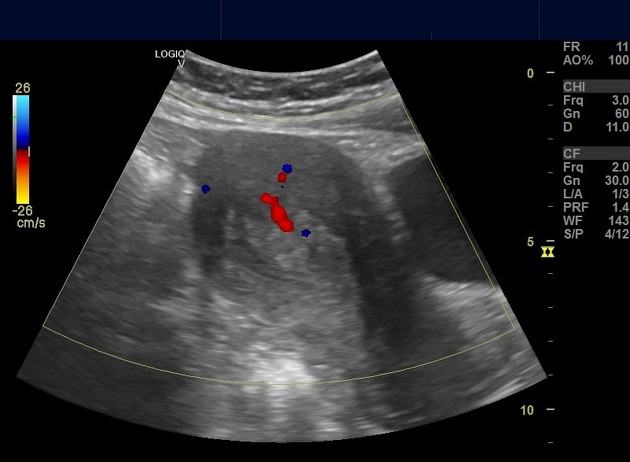

Polyp nội mạc tử cung

» Thông tin: Nữ giới – 40 tuổi.

» Lâm sàng: Rong kinh.